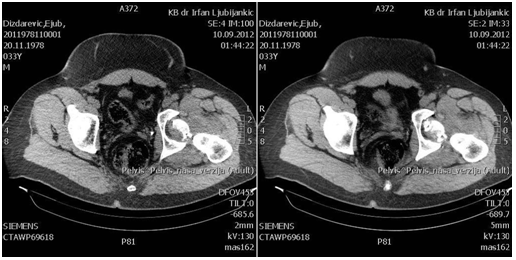

The patient at the age of 34 and 150kg of body weight suffered left hip posterior dislocation with femoral head fracture in car crash accident. The patient had been admitted to hospital after midnight. The mechanism of injury goes as follows: axial force and flexion in the hip caused by impact of the car. The left leg clinically observed is in painful extension, with minimal movement, strong pain and shortened leg. X-rays shows posterior hip joint dislocation and fracture of the femoral head. Closed reduction under anesthesia was unsuccessful. 3D CT reconstruction that had been taken before proceeding to open procedure shows posterior hip dislocation with femoral head fracture above fovea involving weight bearing portion- Pipkin type II fracture dislocation.

Preoperative x-rays, CT scans and 3D CT reconstructions in emergency department are presented as follows (Figure 1-5).

Figure 2 Preoperative CT scans.

Figure 3 Preoperative CT scans.